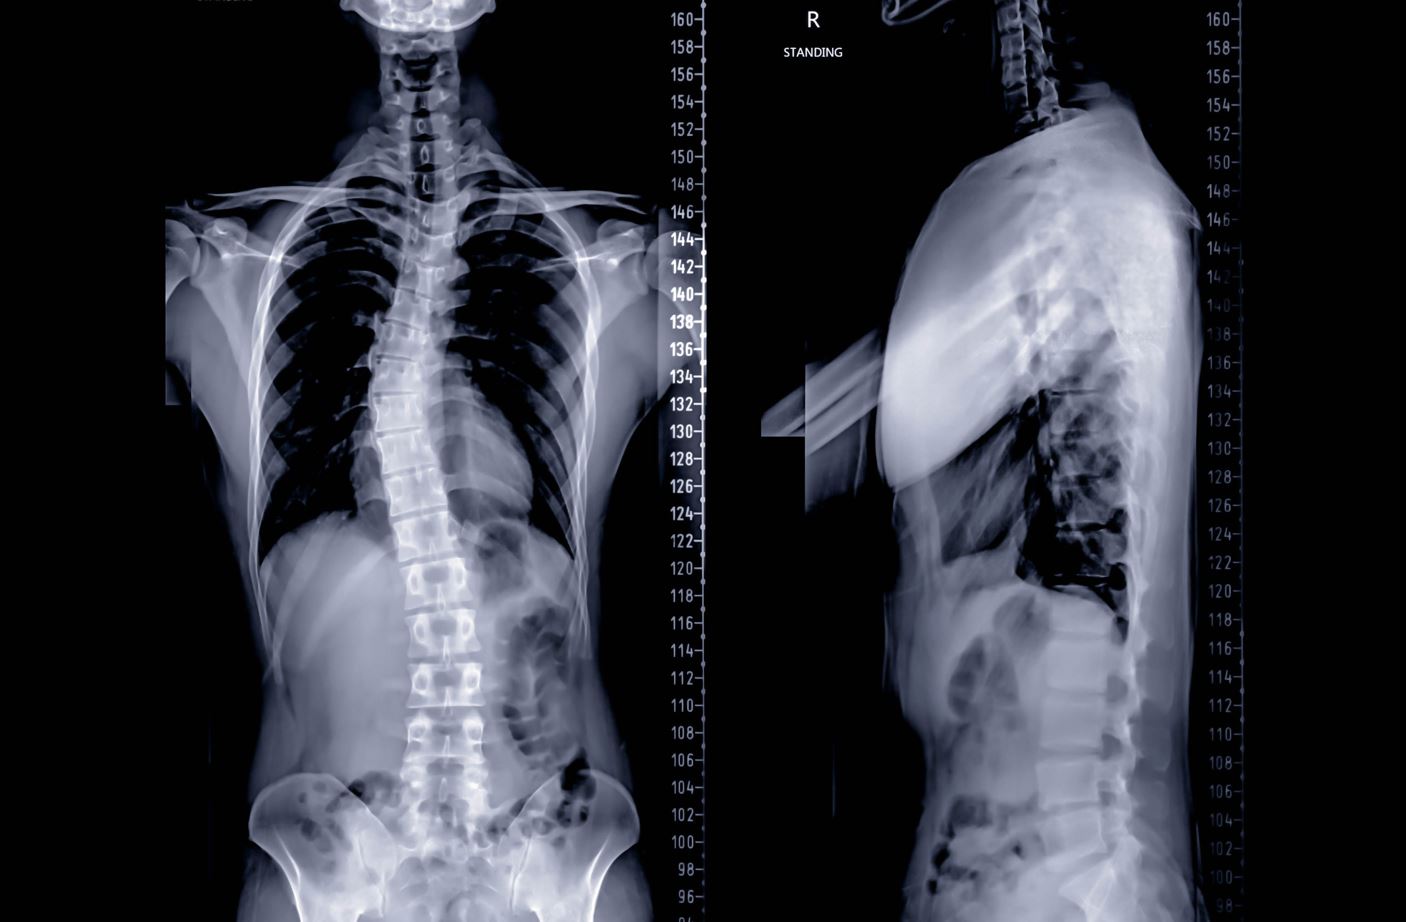

x-ray showing scoliosis of the spine and malalignment syndrome

Scoliosis is a common cause of malalignment syndrome.